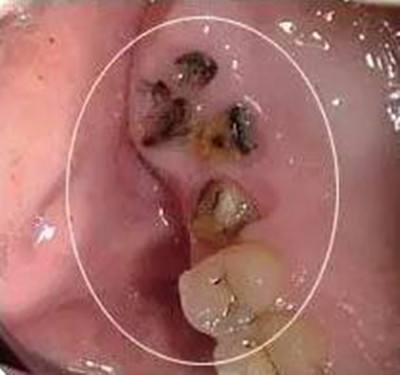

2、龋病。如果口腔内有蛀牙(龋齿),应该及时补牙,当浅龋、中龋的时候,没有不适症状,往往被忽视,在怀孕过程中,龋齿可能会发展为深龋,甚至牙髓炎。当深龋的时候,当食物进入牙洞后,容易引起明显的刺激痛;如果发展到牙髓炎,疼痛就非常明显了,无需刺激,牙齿会不定时的疼痛,尤其晚上疼痛更加明显,半夜因为牙疼来医院就诊的孕妇大多就是这种情况。

5、残根残冠。对于没有保留价值的残根残冠,建议提前拔除,以免孕期发生根尖炎;对于有保留价值,可以修复的残根残冠,要做好根管治疗,如果时间充裕,孕前做好冠修复,如果时间比较紧张,可以等生完孩子再做冠修复。